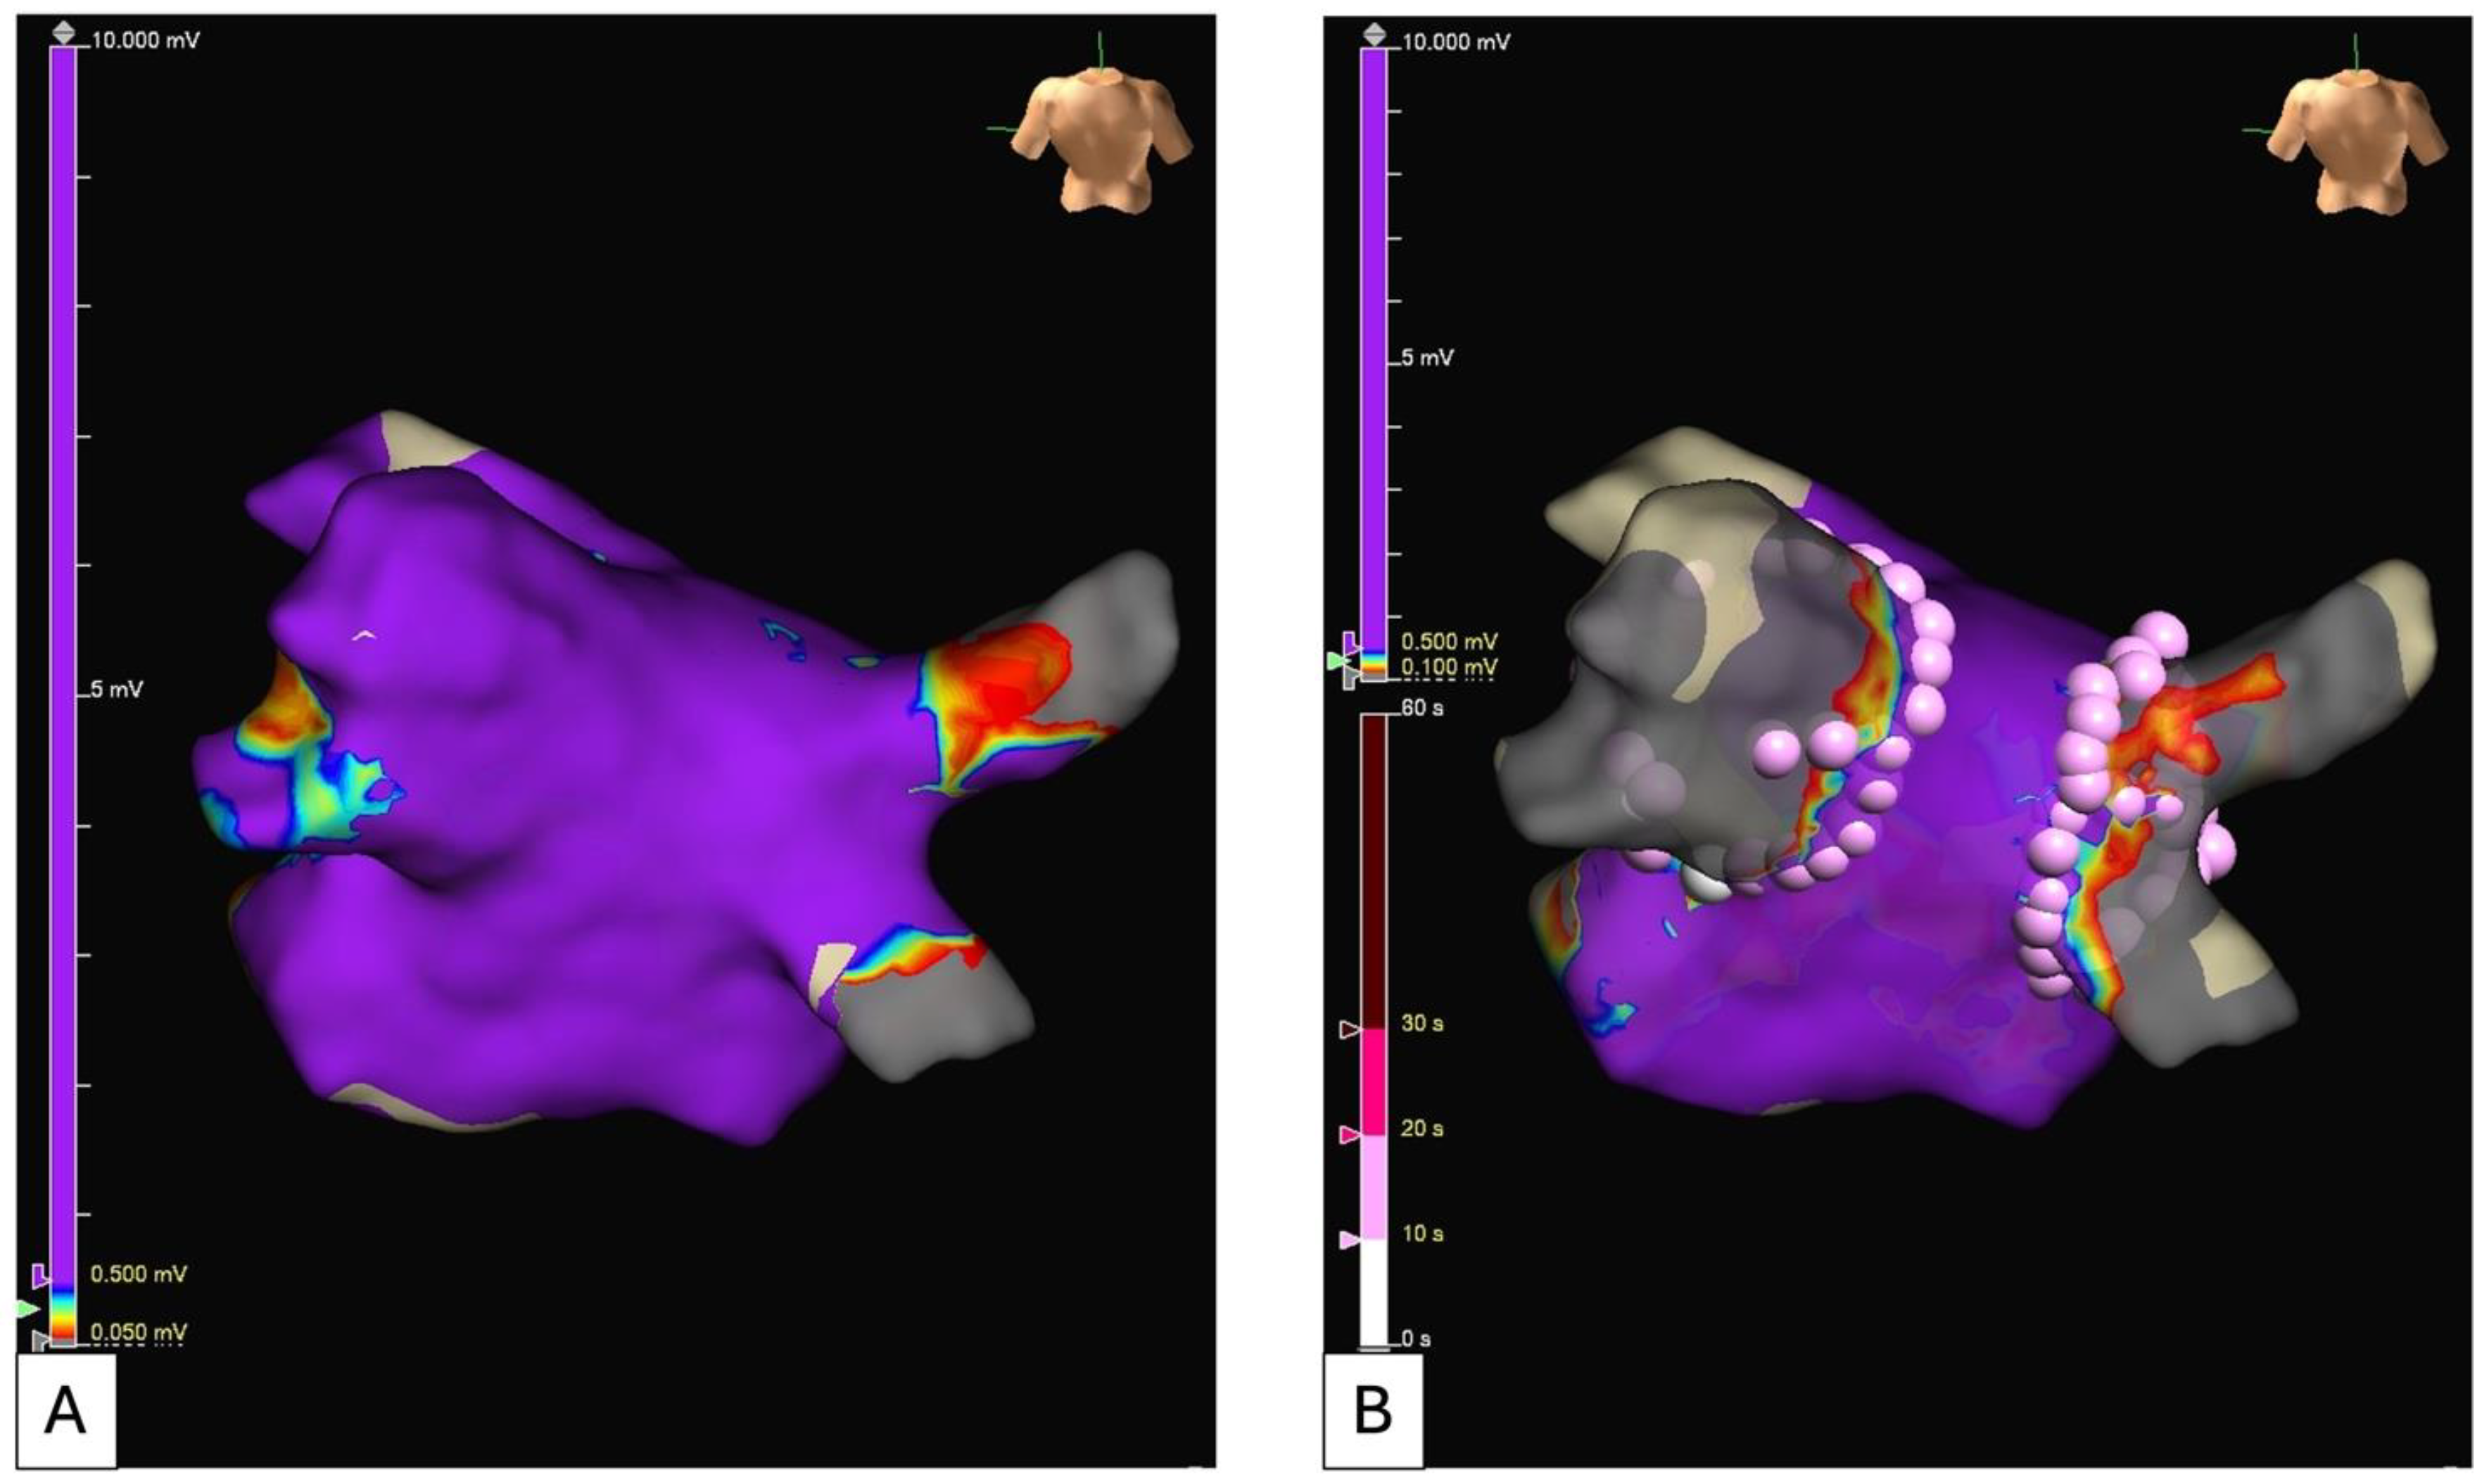

5.2. Electroanatomical Substrate Modification (Low Voltage and Complex Fractionated Electrograms Ablation)

- Rolf, S.; Kircher, S.; Arya, A.; Eitel, C.; Sommer, P.; Richter, S.; Gaspar, T.; Bollmann, A.; Altmann, D.; Piedra, C.; et al. Tailored Atrial Substrate Modification Based on Low-Voltage Areas in Catheter Ablation of Atrial Fibrillation. Circ. Arrhythmia Electrophysiol. 2014, 7, 825–833. [Google Scholar] [CrossRef] [PubMed]